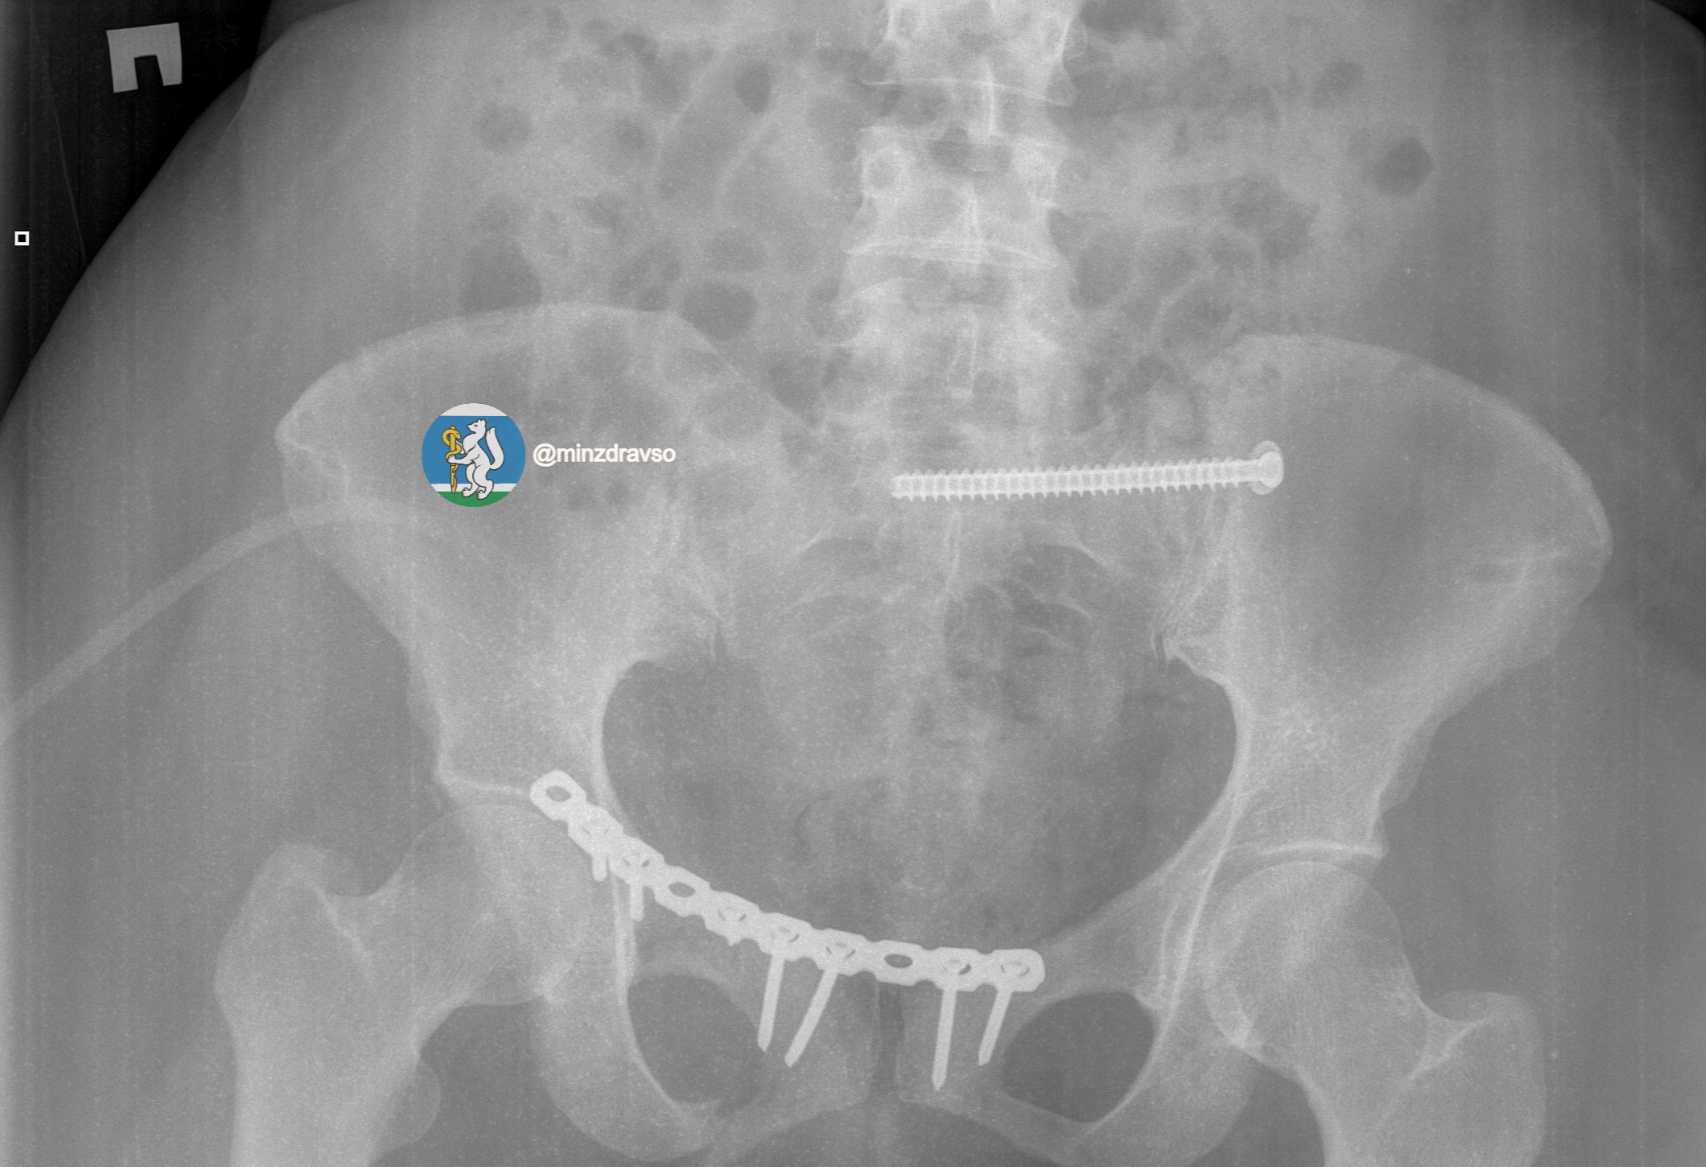

В течение первых 15 минут были проведены все необходимые исследования. Врачи диагностировали тяжелую политравму, включающую закрытую черепно-мозговую травму, ушиб головного мозга, повреждение челюстно-лицевых костей, ребер, двусторонний пневмоторакс, оскольчатый перелом правой ключицы и раздробленные кости таза. Крайне тяжелое повреждение таза представляло высокий риск массивной кровопотери, поэтому борьба за жизнь пациентки началась с немедленной стабилизации ее состояния.

«Пострадавшей оказали помощь, которая отвечает всем современным требованиям к лечению политравмы. Чтобы стабилизировать зоны переломов и купировать болевой синдром, врачи скрепили отломки костей всех поврежденных сегментов костей и таза аппаратами внешней фиксации. Большую роль сыграл мультидисциплинарный подход: спасти пациентку удалось благодаря совместной работе анестезиологов-реаниматологов, травматологов-хирургов и нейрохирургов», – рассказал заведующий травматологическим отделением Городской больницы №36 «Травматологическая», к.м.н. Евгений Козлов.

Профессионализм и опыт врачей, их высочайшая квалификация и плановое совершенствование экстренной медицинской помощи в Свердловской области позволили пациентке получить второй день рождения. Тактика врачей позволила купировать шоковое состояние и подготовить организм к основному хирургическому этапу. Череду вмешательств завершил демонтаж аппаратов внешней фиксации таза и установка внутренних металлофиксаторов на ключицу и кости таза.